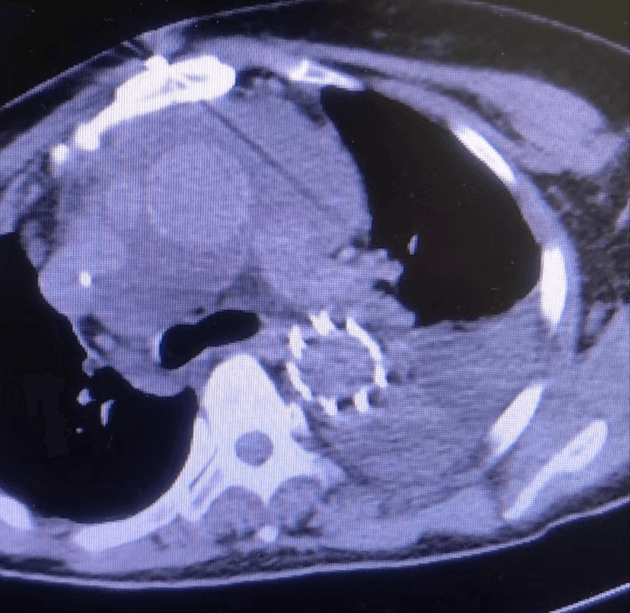

近日,我院急诊科会诊来了一位60岁女性患者,患者诉胸背部疼痛4小时余,疼痛剧烈,不能忍受,来院时血压260/135mmHg,于当地县医院行大血管CTA检查,提示主动脉夹层。新型冠状病毒感染未完全康复的值班医生一路小跑都气喘吁吁前往急诊科会诊,一边咳嗽一边问诊,由于患者病情危急,请示心外科武小刚科主任后分析:患者系主动脉夹层动脉瘤(A型),降主动脉近段可见明显破口,升主动脉明显增宽,根据超声提示,目前考虑升主动脉已有新的破口,需急诊行外科手术治疗。与家属沟通后积极降压、止痛、备血等,进入夹层绿色通道,经过快速的术前准备,患者及早进入手术室,术中仔细剥离血管及周围组织,小心翼翼的分离出受累血管,严格控制血压,避免因血压过高导致血管破裂,建立体外循环术中探查升主动脉可见1cm破口,验证了术前的判断;剪除掉破损血管,植入人工血管,仔细吻合每一根血管,既不能让吻合口过小导致血液供应不足,也不能让吻合口出血,一台“升主动脉置换+全弓置换+象鼻术”需要经过长达6~8小时高精度操作,对医生的耐力和精神都是一种考验,经过6小时的手术,顺利拆除“炸弹”。主刀医师从手术室出来,已经是凌晨2点钟,脱掉早已被汗水浸透的手术衣,瘫软的坐在椅子上,但患者转危为安,再大的疲惫都是值得的。

术后复查恢复良好